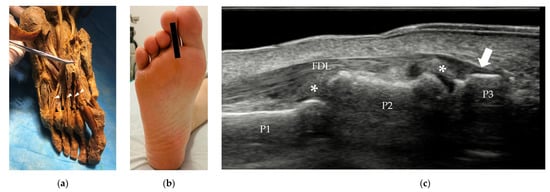

3.2.2. Tendons and Muscles of the Plantar Foot

| Tenosynovitis | / | tendon sheath distension with surrounding effusion, “target” sign in transverse view |